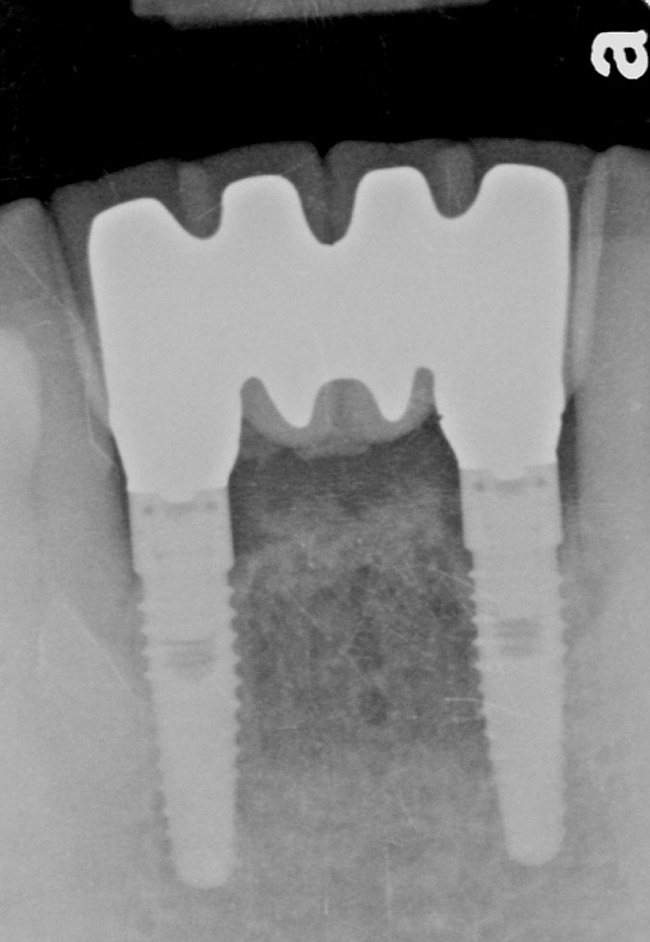

A 53-year-old male presented with localized advanced periodontal disease of the mandibular incisors. Teeth Nos. 23 to 26 exhibited Class II mobility because of advanced bone loss (Figure 1). The teeth had migrated out of position over the years, and a diastema had developed between No. 24 and No. 25 (Figure 2). The patient complained about the poor esthetic appearance of these teeth, and he was able to perceive their loss of strength on function as a result of their mobility.

Preoperatively, 1 g of amoxicillin was administered. Using local anesthesia (lidocaine 1:100,000 epinephrine), extractions of teeth No. 23 to No. 26 were performed without raising a flap and with gentle luxation to preserve the remaining facial osseous plate. The sockets were curetted prior to implant placement. A vacuum-formed surgical guide, fabricated based on a diagnostic wax-up of the desired tooth positions for the subsequent fixed prosthesis, was used during implant placement. Osteotomies were performed at sites No. 23 and No. 26 and positioned toward the lingual aspects of the sockets (Figure 3A and Figure 3B). Two tapered implants (OsseoTite™ 313, BIOMET 3i™, Palm Beach Gardens, FL) measuring 3.25 mm x 13 mm were placed. Conical prosthetic abutments (3-mm height) were used to facilitate joining the two implants in a screw-retained fixed partial denture (Figure 4). A laboratory-processed acrylic-resin provisional restoration was altered to allow connection to the temporary cylinders. The provisional was placed into the vacuum-formed surgical guide that was now used to maintain the provisional in the correct 3-dimensional position (Figure 5) while being attached to the temporary cylinders with acrylic resin intraorally. Once a sufficient amount of acrylic resin was placed to secure the cylinders to the provisional, it was removed from the mouth and its contours were completed at the laboratory bench (Figure 6A). The two central incisor sockets were grafted with small-particle allograft material (Puros® Allograft, Zimmer Dental, Carlsbad, CA) to maintain gingival architecture beneath two ovate pontics (Figure 6B). The provisional restoration was inserted and the screws tightened to 20 Nt-cm of torque.

The patient was given postoperative instructions and advised to maintain a soft diet for 6 to 8 weeks to protect the implants. The patient was followed weekly for the first 3 weeks and monthly thereafter. After 4 months of healing, the provisional restoration was removed and the soft tissues were examined. Mature, keratinized gingival tissues were present facially, lingually, and interproximally. Nonkeratinized tissue could be seen at the tissue surfaces of the ovate pontics and in the intrasulcular regions of the implant abutment units. No clinical probing depths beyond 1 mm were found adjacent to the abutments. The healed tissue represented an acceptable clinical result especially in light of the gap that had been present at the time of implant placement (Figure 7A and Figure 7B). Final impressions were made, and the permanent ceramo-metal screw-retained prosthesis was placed within 8 weeks (Figure 8).

Figure 1  Preoperative clinical condition.

Figure 1

Figure 2  Preoperative radiograph shows healthy cuspids and advanced periodontal disease on the four mandibular incisors.

Figure 2

Figure 9  The 4-year postoperative radiograph.

Figure 9